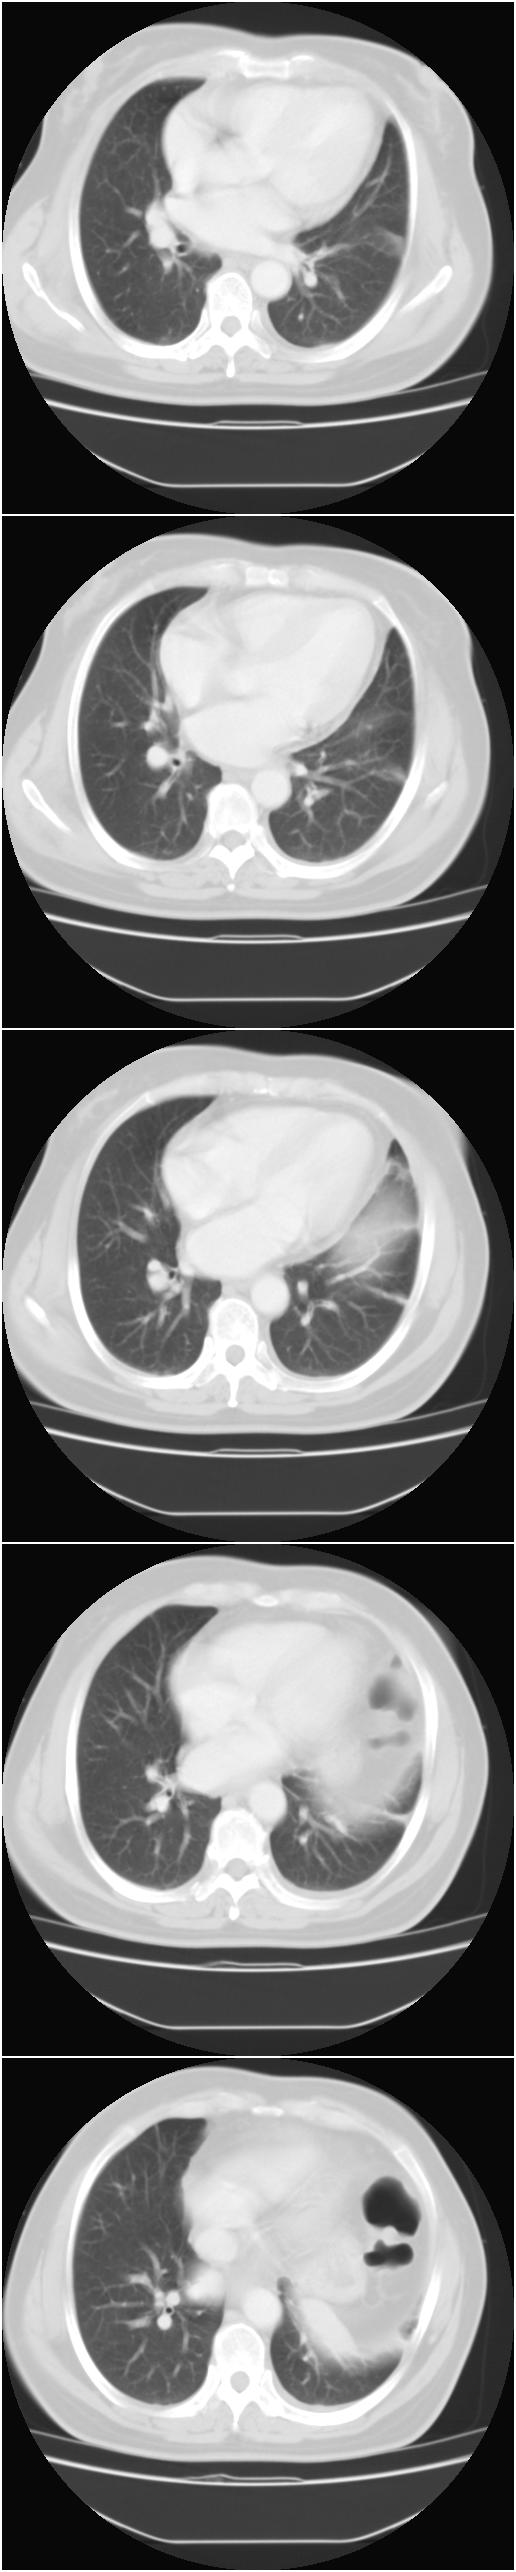

标题: CT13028:女,56岁。咳嗽、气促一月,咳血一周。CT值增加约30 [打印本页]

标题: CT13028:女,56岁。咳嗽、气促一月,咳血一周。CT值增加约30

考虑左上肺癌(周围型)伴左肺门及纵隔转移(主肺动脉窗旁病灶可能为肿大并坏死的淋巴结),不除外纵隔型肺癌

支持纵隔旁型肺癌伴主动脉弓\\主肺动脉及左侧头壁动脉受侵.

考虑左肺中心性肺癌并纵隔淋巴结转移,累及左肺动脉及左侧头臂静脉.但不除外纵隔恶性肿瘤累及肺组织.

考虑左肺中心性肺癌并纵隔淋巴结转移,纵隔恶性肿瘤累及肺组织的可能性小,因为后者一般不会导致横膈上抬。

考虑左侧中央型肺癌伴左肺上叶肺不张及前纵隔淋巴转移。

1)考虑为:左肺上叶中心型肺癌伴左肺上叶阻塞性肺炎、节段性肺不张,左肺门及纵隔淋巴结转移。2)左侧少量胸腔积液。